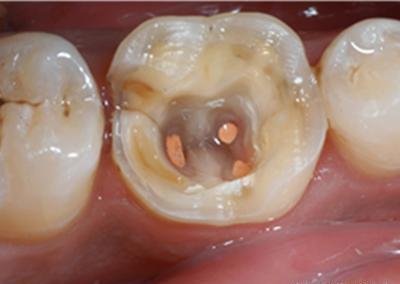

根管治疗是针对牙疼产生的病因,处理牙神经疼痛,长期保留牙齿的最佳方法。治疗时,医生首先在牙齿上钻一个洞(在打麻药的情况下),减轻根管内的压力,将炎性分泌物释放出来。效果立竿见影,患者马上就感觉牙齿不疼了。

然后,医生会用专业的器械将根管内感染坏死的神经、血管组织清理出来,再用特殊的工具将根管扩大成形,消毒干净。最后,等患牙完全没有不适症状时,再用专门的材料将根管非常致密地充填起来,使牙齿的外形恢复完好。